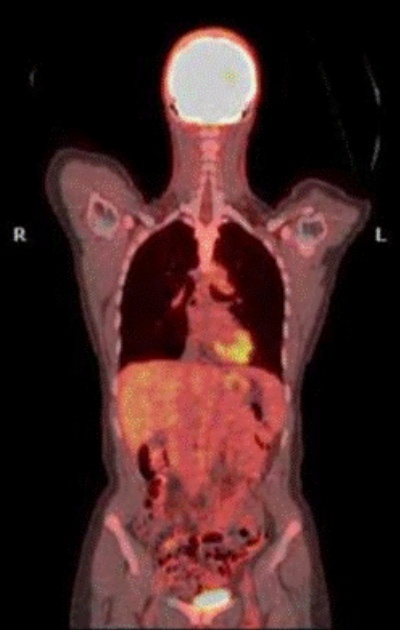

PET scan adalah sebuah terobosan mutakhir dalam dunia kedokteran nuklir yang memungkinkan para dokter melihat secara langsung fungsi dan metabolisme sel tubuh.

Berbeda dengan pencitraan lain seperti CT scan atau MRI yang hanya memberikan gambaran struktur organ, PET scan (Positron Emission Tomography) memberikan informasi vital tentang aktivitas biokimia di tingkat seluler.

PET scan adalah alat pencitraan medis non invasif menggunakan teknologi Positron Emission Tomography yang berfungsi untuk mendeteksi aktivitas metabolik atau fungsi sel-sel tubuh dalam kondisi normal atau tidak.

Alat ini bekerja dengan cara melacak distribusi zat radioaktif dosis rendah disebut radiofarmaka yang dimanfaatkan sebagai tracer di dalam tubuh. Radiotracer ini akan tertahan pada sel yang memiliki aktivitas metabolik tinggi, seperti sel kanker, yang kemudian dideteksi oleh mesin PET scan untuk menghasilkan gambar 3D yang detail.

4. Pembentukan Gambar

Mesin PET akan memproses data yang didapat untuk menghasilkan gambar 3D yang menunjukkan di mana sel-sel yang aktif secara metabolik berada, aktivitas metabolik yang tinggi dari F18-FDG perlu diwaspadai adanya sel-sel kanker.

Salah satu aplikasi paling vital dari PET scan dibidang onkologi adalah untuk deteksi Kanker, karena biasanya sel kanker menunjukkan metabolisme glukosa yang lebih tinggi dibandingkan jaringan normal, juga menentukan stadium kanker (cancer staging), disamping beberapa manfaat yang lain termasuk menilai respons terapi ad interim (di tengah-tengah pengobatan kanker).

Pemeriksaan ini dapat melihat sejauh mana kanker telah menyebar (metastasis) di tubuh seperti ke kelenjar getah bening atau organ lain di seluruh tubuh.